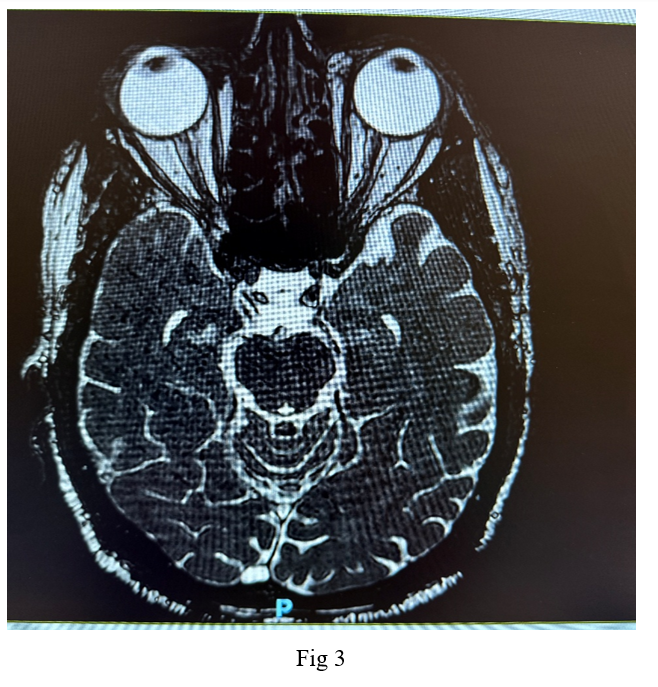

Imaging studies, including a native CT scan of the brain, MRI of the brain, and MRI of the orbit without contrast, revealed no pathological findings. Additionally, laboratory tests, including a complete blood count, erythrocyte sedimentation rate, C-reactive protein, fasting blood sugar, glycated hemoglobin, thyroid function tests, kidney function tests, B12 levels, blood glucose, and blood pressure, were all within normal ranges. Following a neurological consultation, he was diagnosed with cluster headache associated with oculomotor nerve palsy.

Neuroimaging, such as Cranial MRI, is essential to rule out structural abnormalities, particularly in patients with symptoms resembling other headache types or conditions like pituitary tumors. Distinguishing cluster headaches from other trigeminal autonomic cephalalgias and primary headache disorders is crucial for appropriate management.

Figure 3